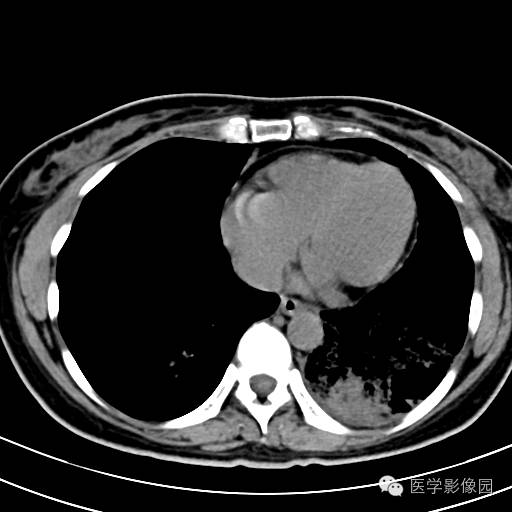

肺叶实变性支气管肺泡癌1例CT影像表现